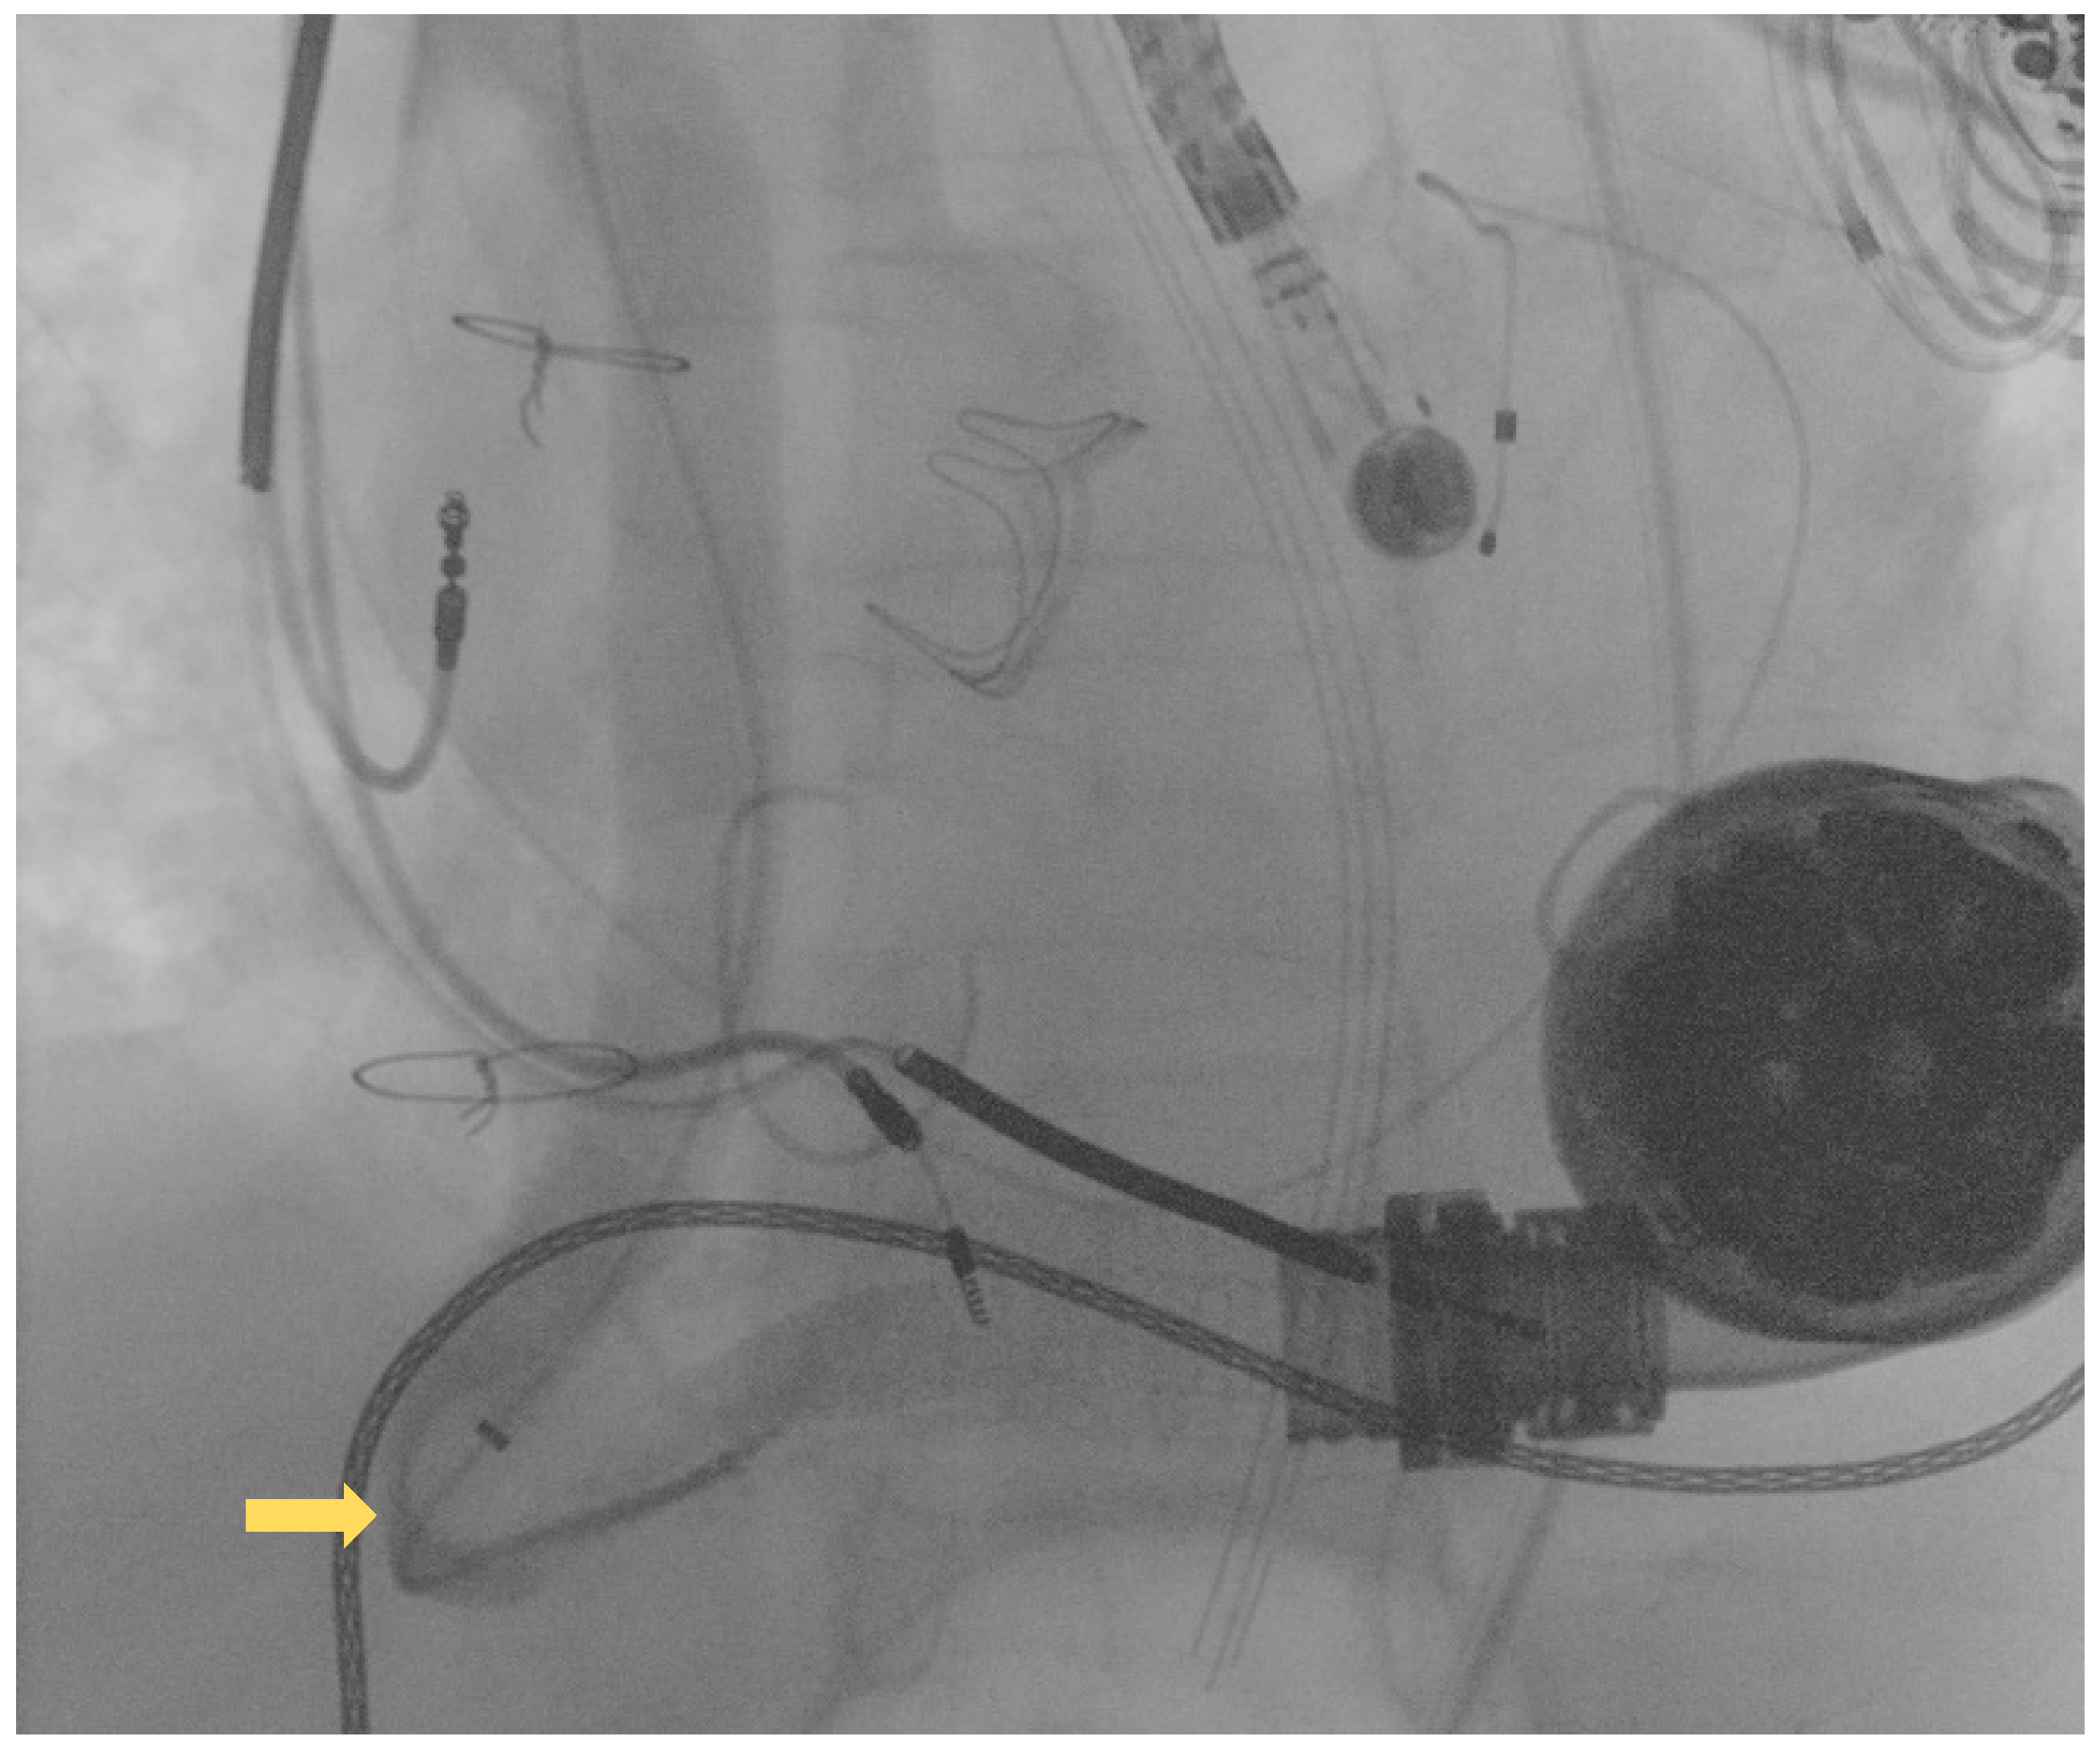

The first guidewire was removed and a 0.035″ × 260 cm stiff guidewire (Amplatz Super Stiff™, Boston Scientific, Natick, MA, USA) was deployed distally. Following this, an “anchoring technique” [8] with a 12 mm balloon located in the proximal tract of the outflow graft was adopted in order to advance the long sheet throughout the kinking. After that, a balloon-expandable 10 × 79 mm endoprosthesis (GORE® Viabahn® VBX) was implanted. Distal anchoring and stent positioning are shown in Figure 3A,B.

Figure 3.

(A) distal anchoring; (B) stent deployment.

Due to severe underexpansion of the implanted stent, several postdilations were performed using peripheral balloons of increasing diameters (MUSTANGTM 0.035″, Boston Scientific) (see Figure 4).

Figure 4.

Postdilation of the implanted stent.